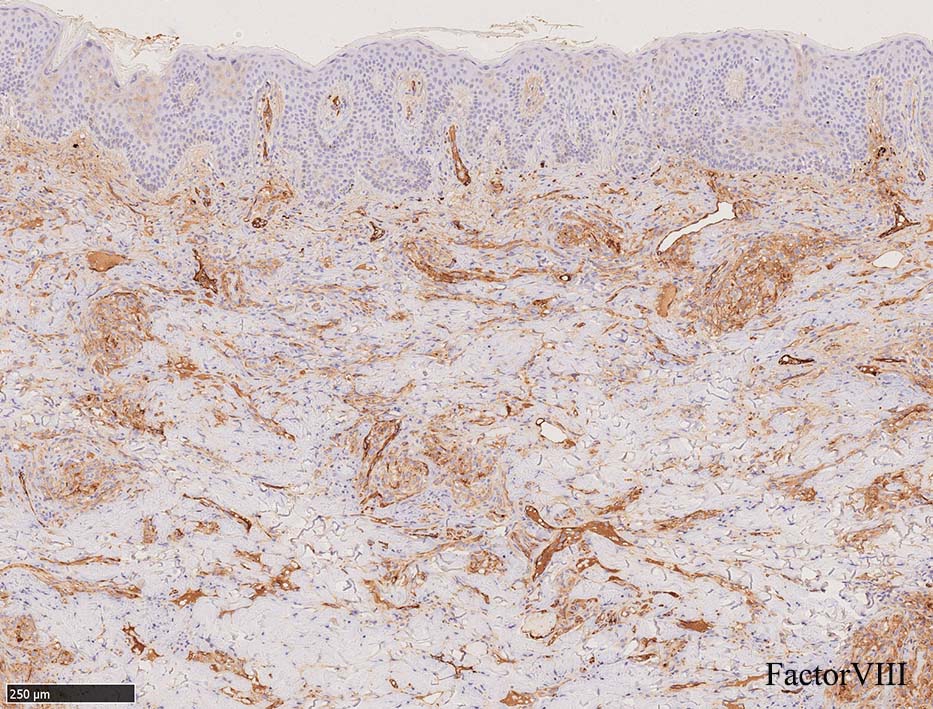

免疫染色, 分子病理学的検査

増生細胞はCD31, CD34, Factor Ⅷ, D2-40などが陽性を示す.

細血管周囲に血管内皮様の紡錘形細胞が増生, 一部に赤血球をいれた裂隙の形成がある. 細胞の異型はみられず, mitosisの増多もない. hemosiderin-laden macrophageが散在する.

病変は真皮内に現局している. 初期斑状病変に相当すると考えられる. 本例では, 特徴とされる形質細胞浸潤増加はみられない.